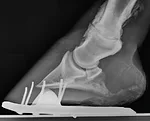

If you’ve suffered from a bone spur, you can imagine how ringbone feels to a horse. Some level of discomfort accompanies each step. Swelling might or might not be present, but one thing is for sure, the bony growth interferes with mobility. The same is true for horses.